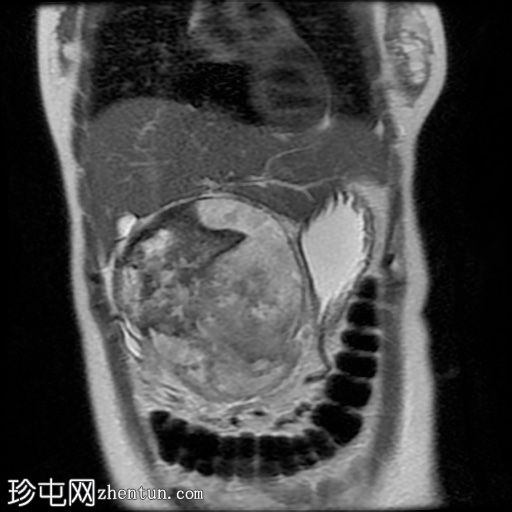

T2加权像

冠状位T2加权像

6.jpg

病灶在T2加权像上呈不均匀高信号,内部区域信号强度不一。

MRCP显示胆总管正常,无胆管扩张或梗阻征象。

主胰管未见,可能由于肿块压迫/取代所致。